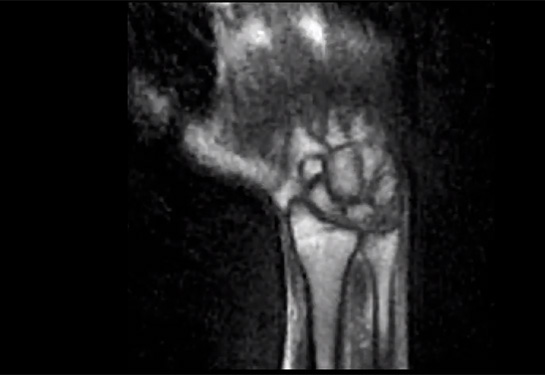

Read MoreA new study led by UC Davis researchers shows that a new, low-field MRI system can create clear videos of moving wrists.